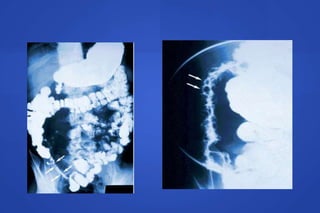

COLITIS ULCEROSA

Enema Opaco

A B